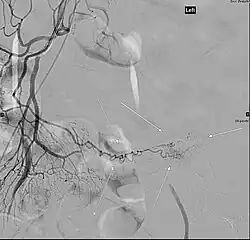

Angiografia klasyczna

Angiografia klasyczna, krwawiący uchyłek Meckela

Klasyczna angiografia zwykle jest wykorzystywana w diagnostyce krwawienia z dolnego odcinka przewodu pokarmowego ze względu na łatwo dostępne końcowe odcinki naczyń tętniczych. W diagnostyce krwawień z górnego odcinka przewodu pokarmowego metoda ma ograniczoną skuteczność ze względu na bogatą sieć połączeń pomiędzy naczyniami. Metoda pozwala wykrywać krwawienie o intensywności utraty krwi 0,5–1,5 ml/min[1]. Czułość diagnostyczna angiografii wynosi około 42–86%, a swoistość sięga 100%[130][1]. Metoda pozwala jedynie na wykrywanie czynnego krwawienia[131]. Jest szczególnie przydatne w wykrywaniu krwawienia z malformacji naczyniowych i uchyłków jelita[131]. Angiografia klasyczna pozwala na przeprowadzenie zabiegów mających na celu zatrzymanie krwawienia, w tym selektywne podanie materiału zatorowego lub leku obkurczającego naczynia. Ze względu na inwazyjny charakter i ryzyko poważnych powikłań angiografii metoda jest ograniczona dla chorych, u których z powodu krwawienia z niestabilnością hemodynamiczną nie można wykonać endoskopii lub u chorych z nawracającymi krwawieniami z przewodu pokarmowego, których źródła nie ustalono metodami endoskopowymi[1].